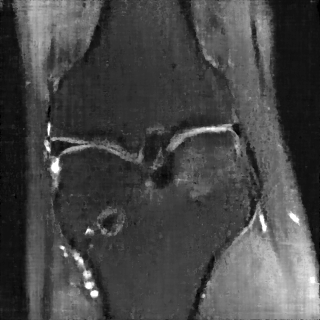

This article presents a novel undersampled magnetic resonance imaging (MRI) technique that leverages the concept of Neural Radiance Field (NeRF). With radial undersampling, the corresponding imaging problem can be reformulated into an image modeling task from sparse-view rendered data; therefore, a high dimensional MR image is obtainable from undersampled $k$-space data by taking advantage of implicit neural representation. A multi-layer perceptron, which is designed to output an image intensity from a spatial coordinate, learns the MR physics-driven rendering relation between given measurement data and desired image. Effective undersampling strategies for high-quality neural representation are investigated. The proposed method serves two benefits: (i) The learning is based fully on single undersampled $k$-space data, not a bunch of measured data and target image sets. It can be used potentially for diagnostic MR imaging, such as fetal MRI, where data acquisition is relatively rare or limited against diversity of clinical images while undersampled reconstruction is highly demanded. (ii) A reconstructed MR image is a scan-specific representation highly adaptive to the given $k$-space measurement. Numerous experiments validate the feasibility and capability of the proposed approach.